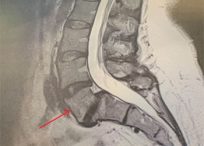

Case Studies